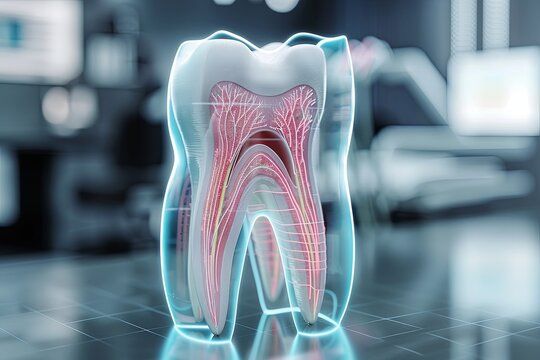

Understanding the Root Canal Process for Seniors

Step 3: Cleaning the Root Canal

The infected pulp is removed from the tooth’s root canal chamber. This prevents bacteria from spreading further and relieves pressure and pain.

Step 4: Sealing the Tooth

After cleaning, the space is disinfected and sealed with a biocompatible filling material to prevent reinfection.